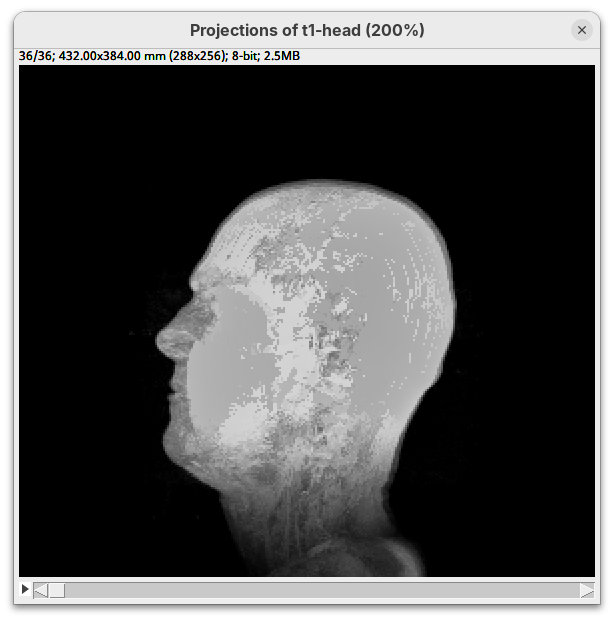

3D Project

This is a simple tool to quickly generate a 3D animation (e.g., 360-degree rotation) from an image stack. There are basic parameters for adjusting the rendering, like projection method and opacity, and for controlling the animation. There’s only a bit of documentation. To try:

- Go to

Image>Stacks>3D Project...and clickOKto generate a basic animation.

As noticeable above, 3D Project doesn’t do so well with our MRI dataset. However, it works OK for fluorescent microscopy images, so I encourage you to try with other datasets in the future.